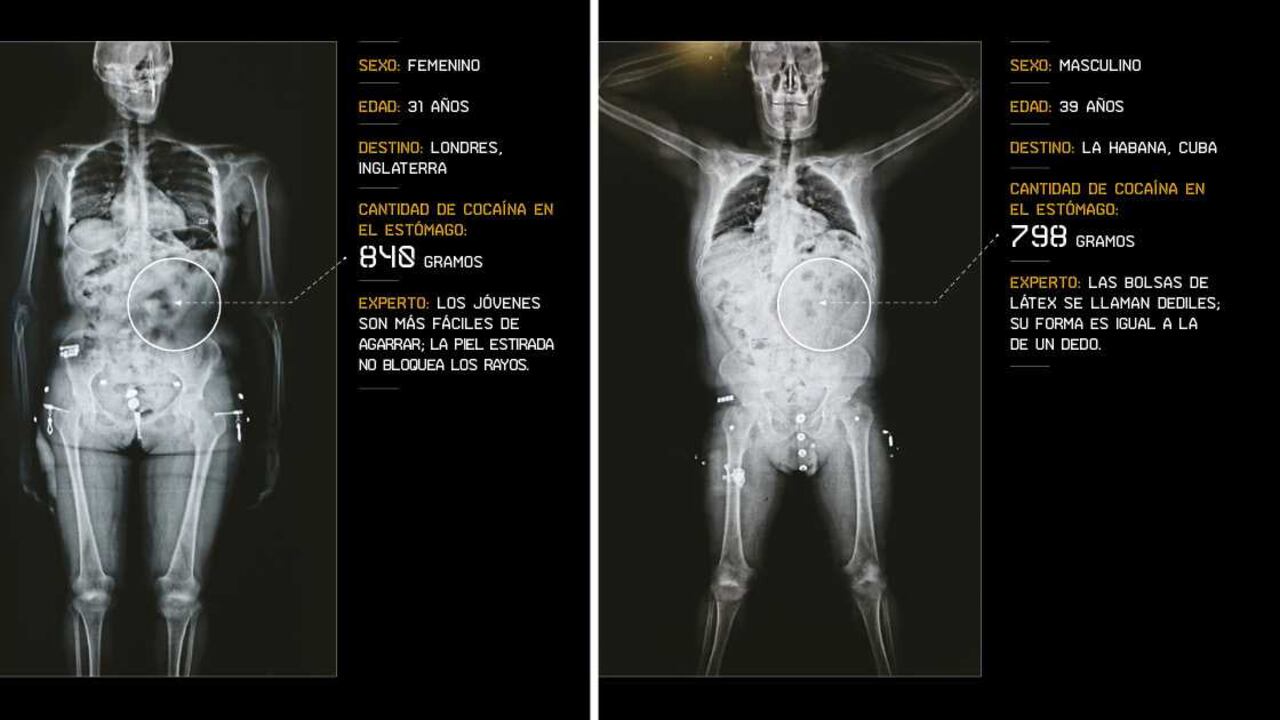

¿Cómo se ven las radiografías de los escáneres de mulas?

Así se ven por dentro los cuerpos de las personas que intentan viajar al exterior con cocaína encapsulada en el estómago, y son pilladas cuando pasan por la máquina Body Sacan del Aeropuerto El Dorado, de Bogotá.